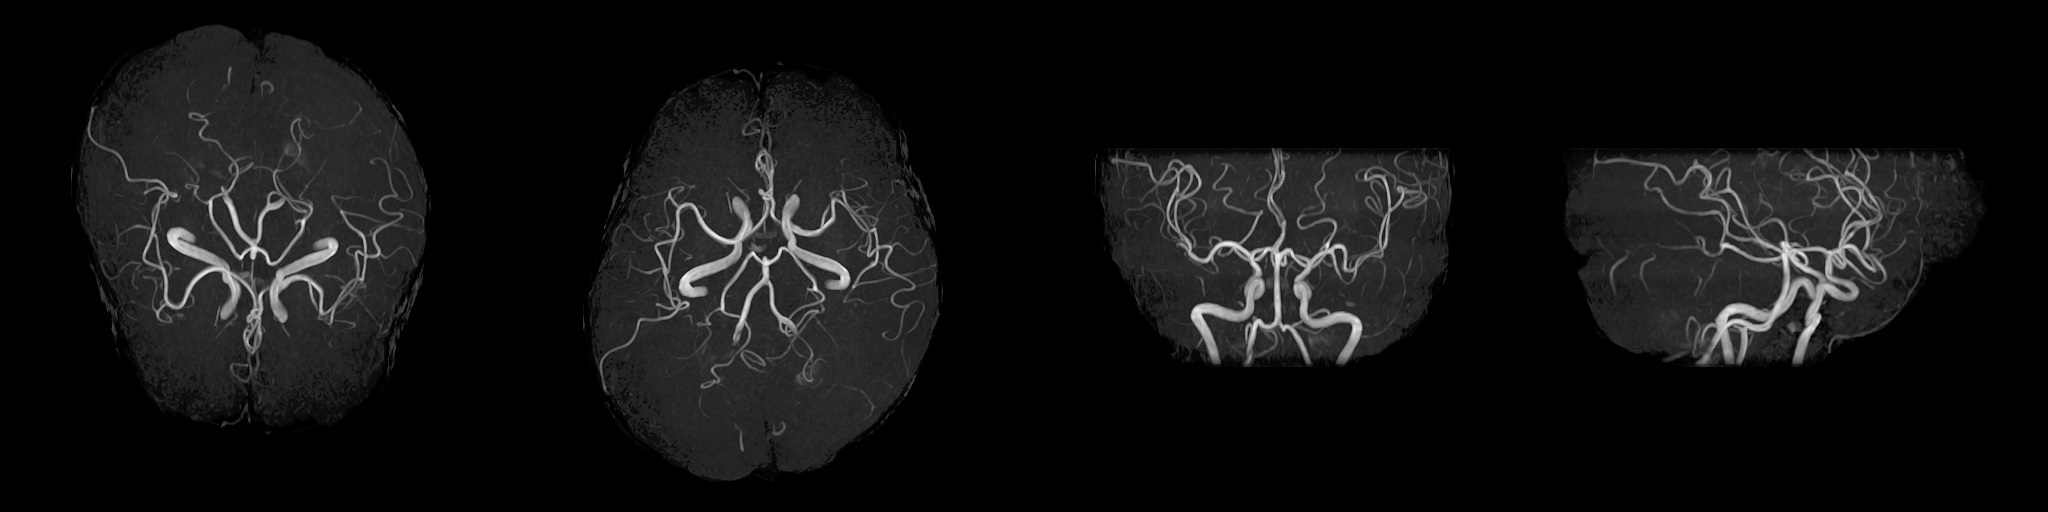

MRI(磁気共鳴画像)装置

2022年2月にMRI装置を更新いたしました。

1.5TのMIR装置(富士フイルムヘルスケア株式会社製「MRイメージング装置 ECHELON Smart」)を導入し、以前よりも短い時間で高画質の撮像が可能になりました。

MRIは体内の断面像を縦、横、ナナメから人体に悪影響を与えずに見ることが出来る装置です。わずかな病変も見逃さない鮮明な画像は腫瘍などの早期発見や健診に威力を発揮します。薬品を全く用いずに血管撮影等が出来るので、患者さんは動かずに横になるだけで苦 痛なく精密検査が受けられます。

MRA

頭部

T1強調像 / T2強調像 / FLAIR像 / T2*強調像